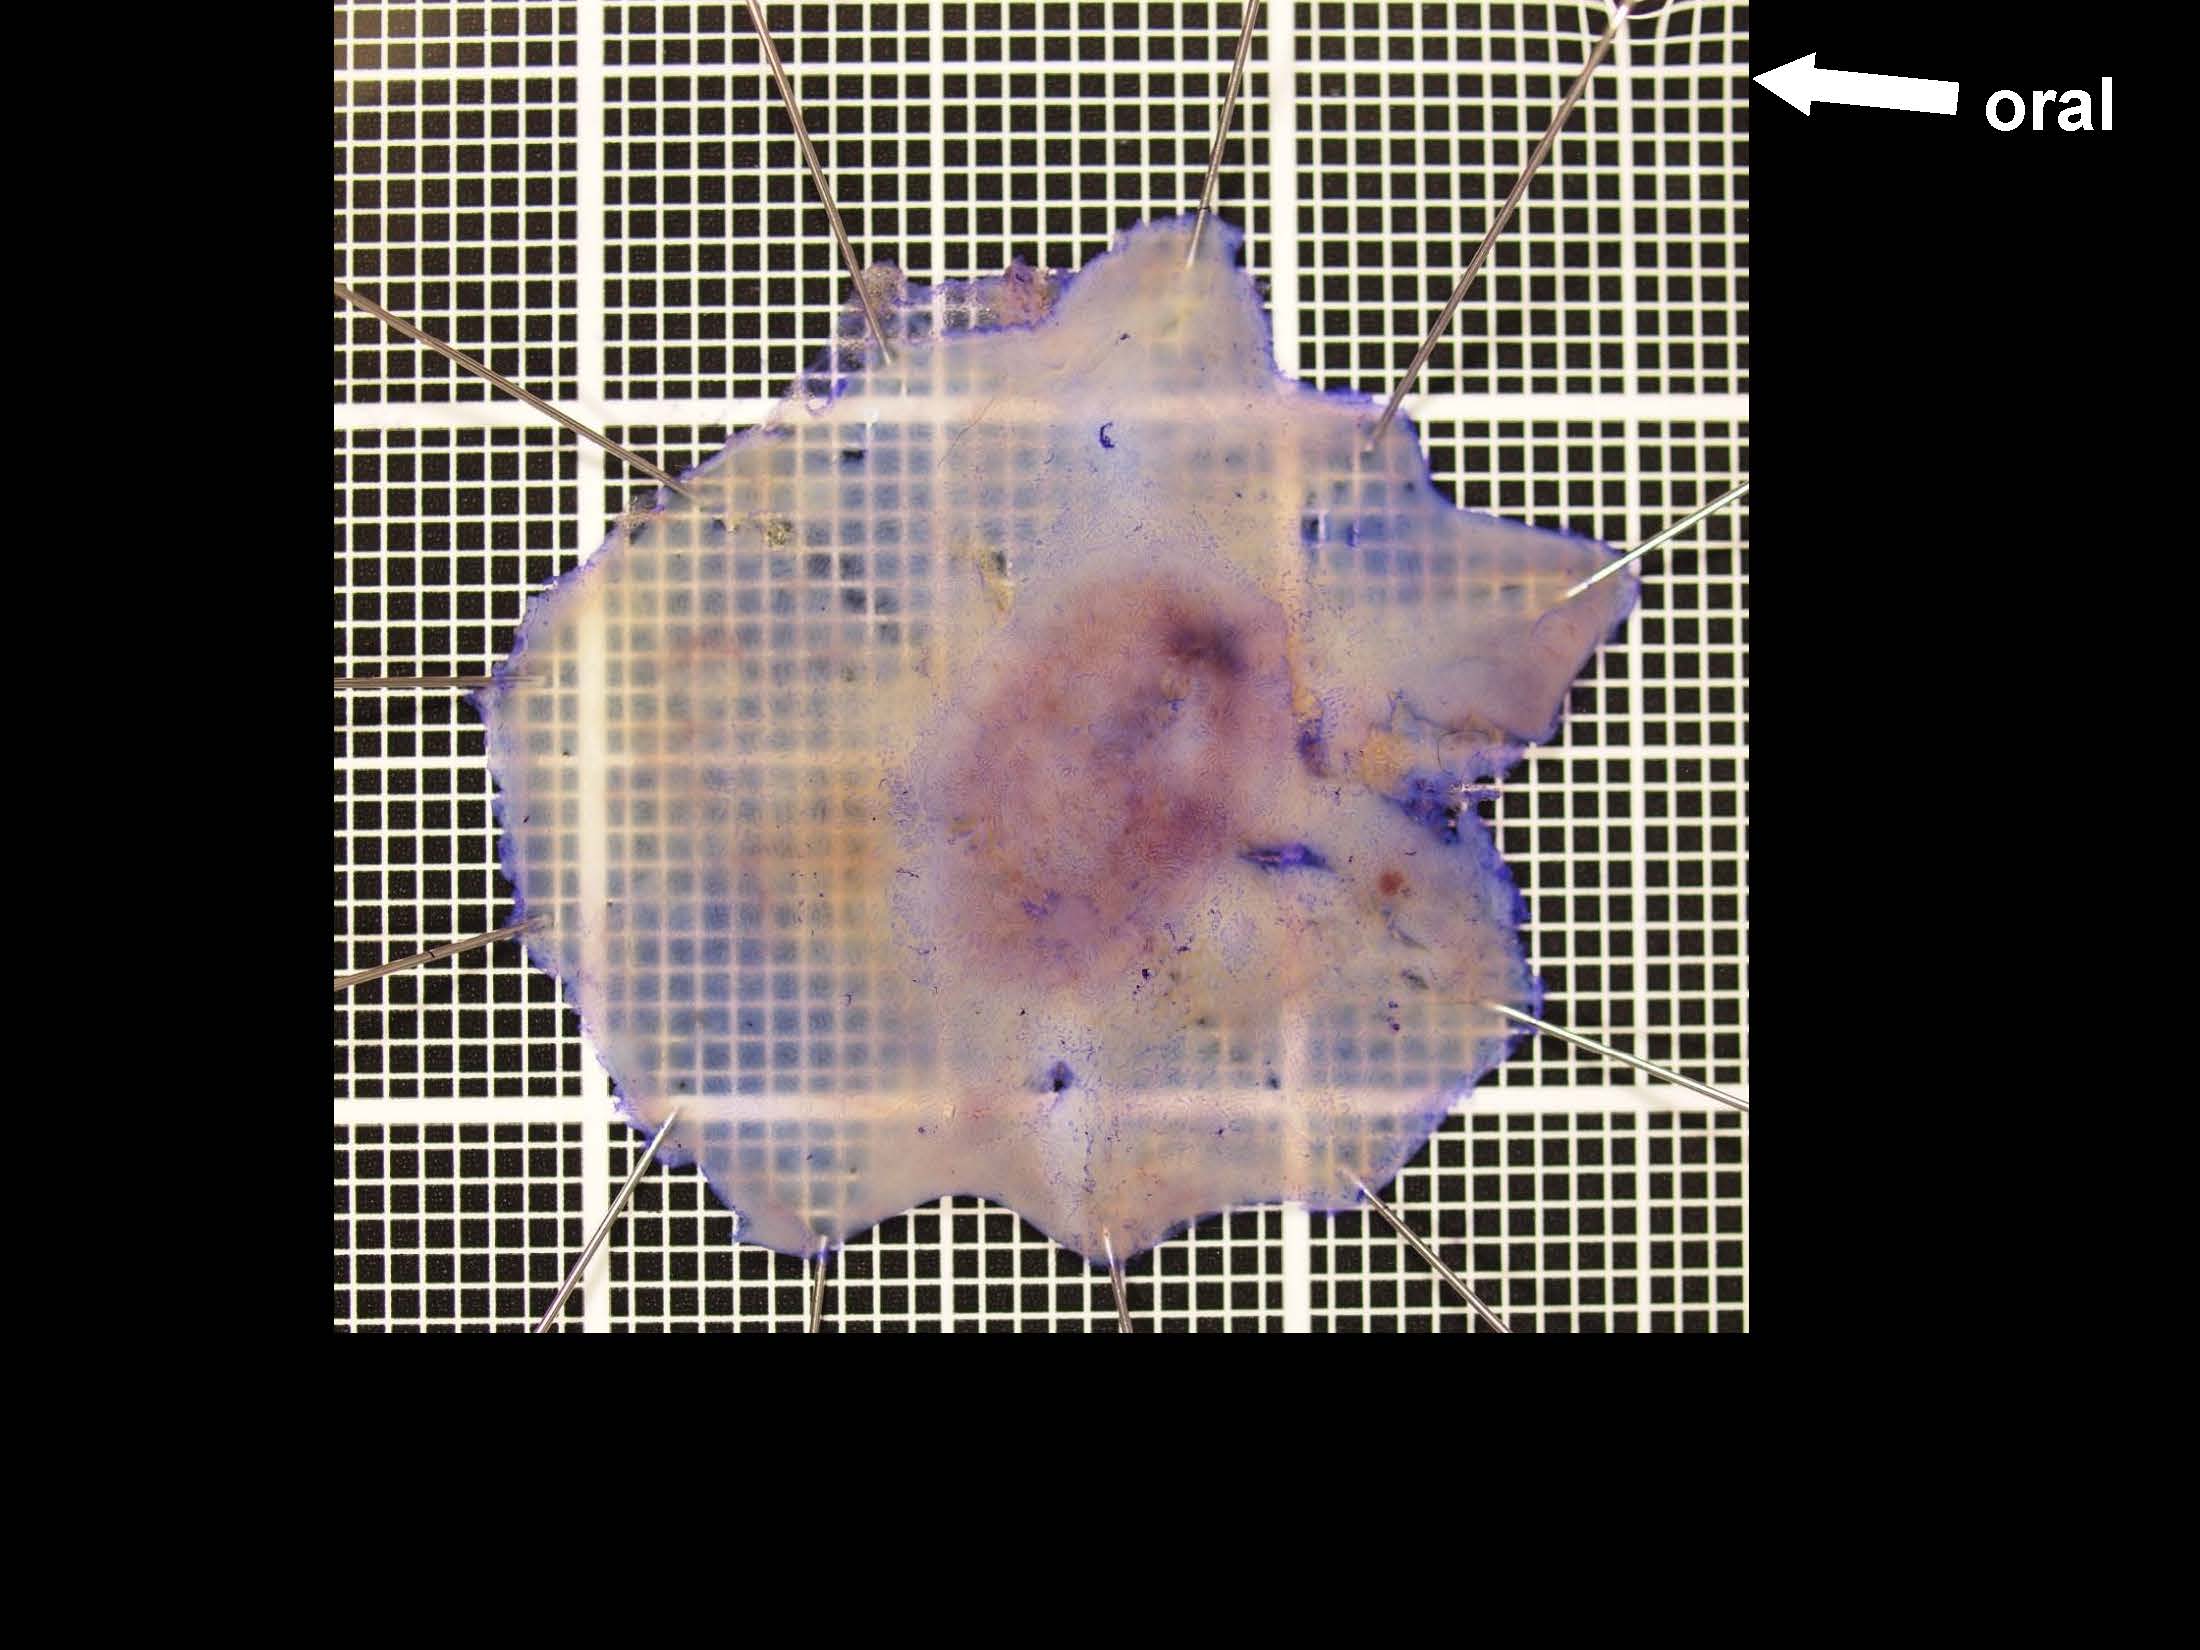

消化管Mapping~大腸~ 2021.10.27

消化管Mapping

消化管Mapping~大腸~

消化器内科

内視鏡検査・治療